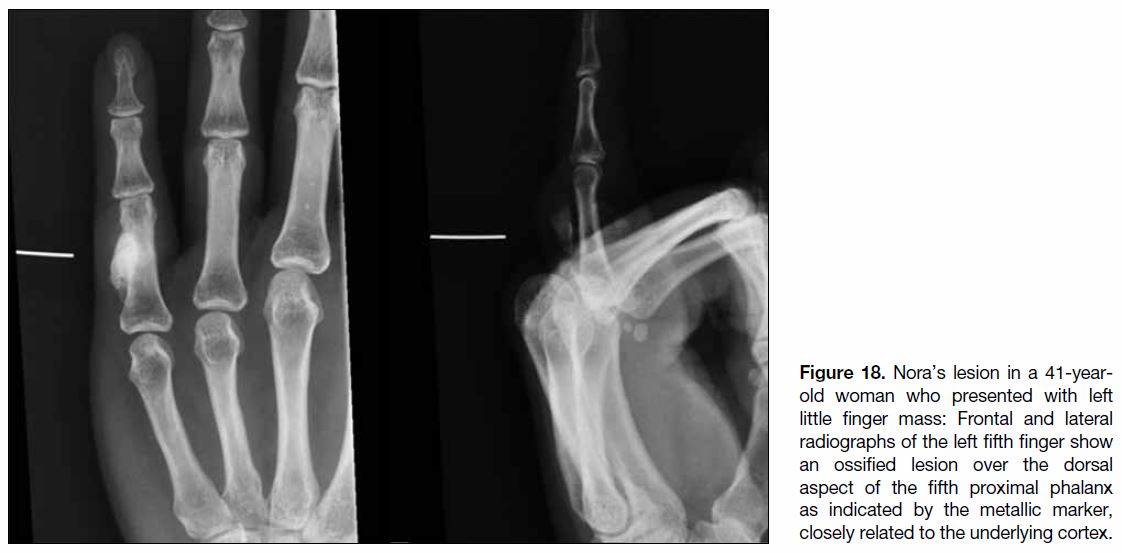

Nora’s Lesion

Nora’s lesions, also known as bizarre parosteal

osteochondromatous proliferations, are benign surface

lesions of the small tubular bones of the hand. Nora’s

lesions typically involve the metaphysis or diaphysis

of the phalanges and metacarpals. They are thought to be due to reactive heterotopic mineralisation arising

from the periosteal aspect of an intact cortex, without

involvement of the medullary canal.[28] Nora’s lesions

occurring under the nail bed are called subungual

exostosis. Radiographically (Figure 18), Nora’s lesions

are seen as broad-based ossified juxtacortical lesions,

without definite cortical or medullary continuation.[32]

Periosteal reaction is usually absent. Radiographs

alone are sufficient for diagnosis as they have a typical

radiographic appearance.[28] Computed tomography

(Figure 19) or MRI (Figure 20) scans are reserved for

cases with inconclusive radiographic findings as they better demonstrate the relationship with underlying

bone. Surgical excision is the treatment of choice but the

recurrence rate is high at 50% to 55%.[33]

Figure 18. Nora’s lesion in a 41-year-old

woman who presented with left

little finger mass: Frontal and lateral

radiographs of the left fifth finger show

an ossified lesion over the dorsal

aspect of the fifth proximal phalanx

as indicated by the metallic marker,

closely related to the underlying cortex.